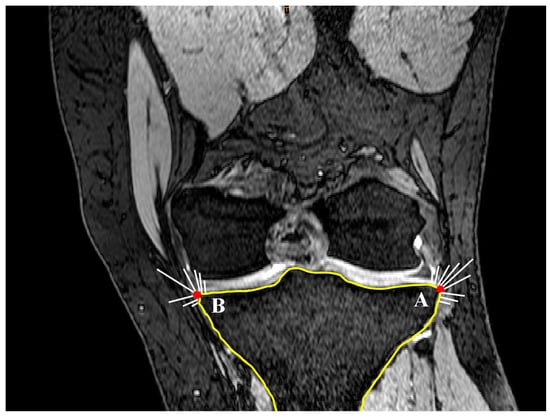

2.2. Coronal Tibial Slope Measurement Method